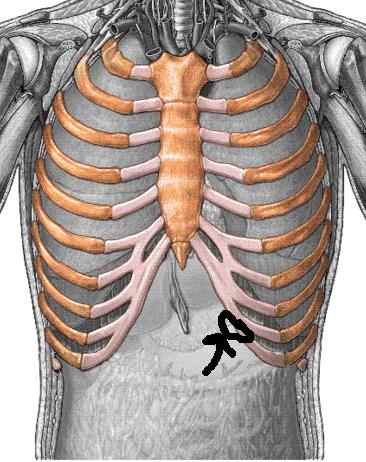

오른쪽 갈비뼈 아래 통증 12가지 원인

지속적이거나 아니라면 급격히 발생한 오른쪽 갈비뼈 통증, 특히나오른쪽 갈비뼈 아래 통증이 계속하여 구성되는 사정이라면 숨을 쉬는 것조차 통증으로 인해 어려울 수 있다고 하는데요.

늑골이라고 명명되며 12쌍을 이루고 있는 갈비뼈는 내부의 심장, 폐, 간 등 주요 장기를 막아주는 역할은 물론 몸의 형태를 계속하고 정상적인 생활을 하는 데 있어 굉장히 귀중한 인체 부위에 부합됩니다.

오른쪽 갈비뼈 아래 통증 주요 원인 12가지